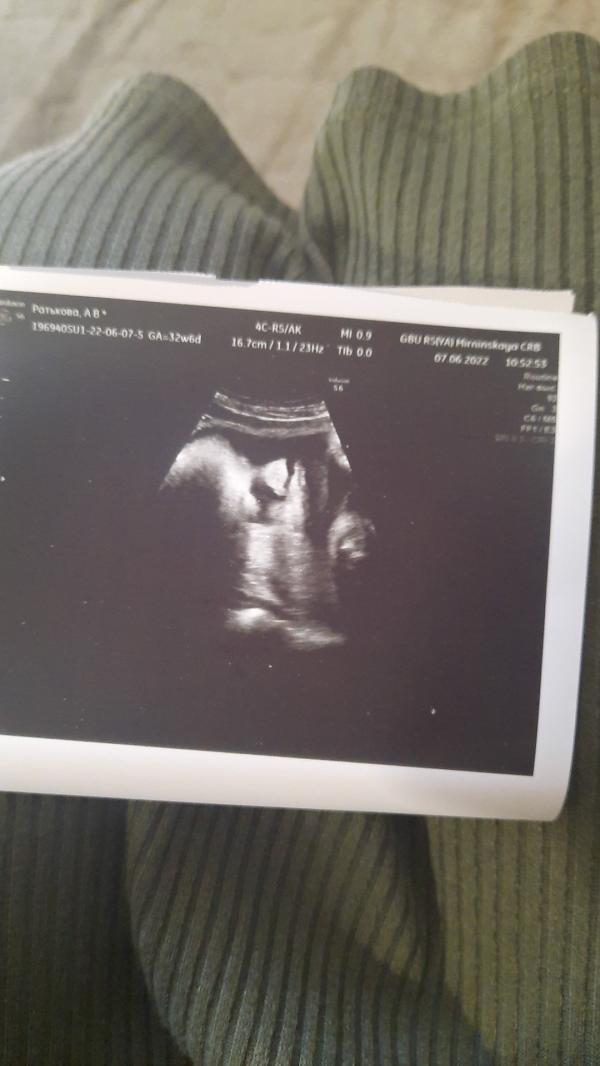

УЗИ: Срок по месячным меньше, вес 2235, мальчик подтвердился! Как выглядит малыш?

Сходила на узи. По месячным срок на 2 дня меньше. Вес 2235. Лежит правильно. Пинает сильно. Мальчик подтвердился. Очень симпатичный малыш. На первом фото кокушки, но втором очень милое личико!